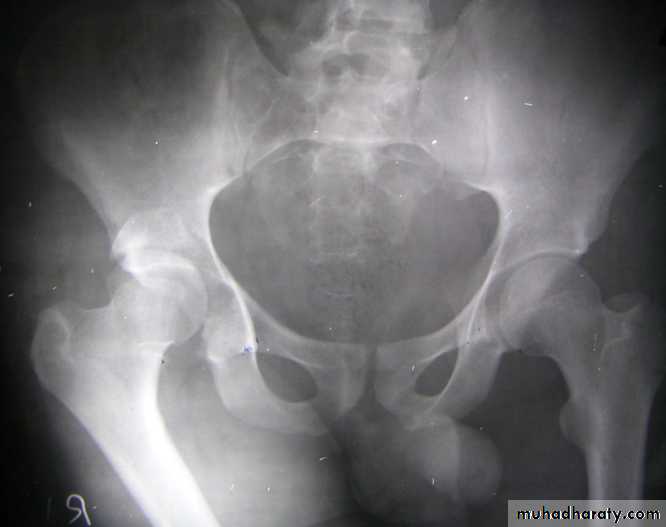

The golden role is to x ray the pelvis in every case of sever injure

and with femoral fracture to include both the hip and knee.

Radiological examinations

X-R AP view we can see the dislocation with or without associated fracture posterior wall of the acetabulum,

or fracture head of the femur,

And neck of femur.